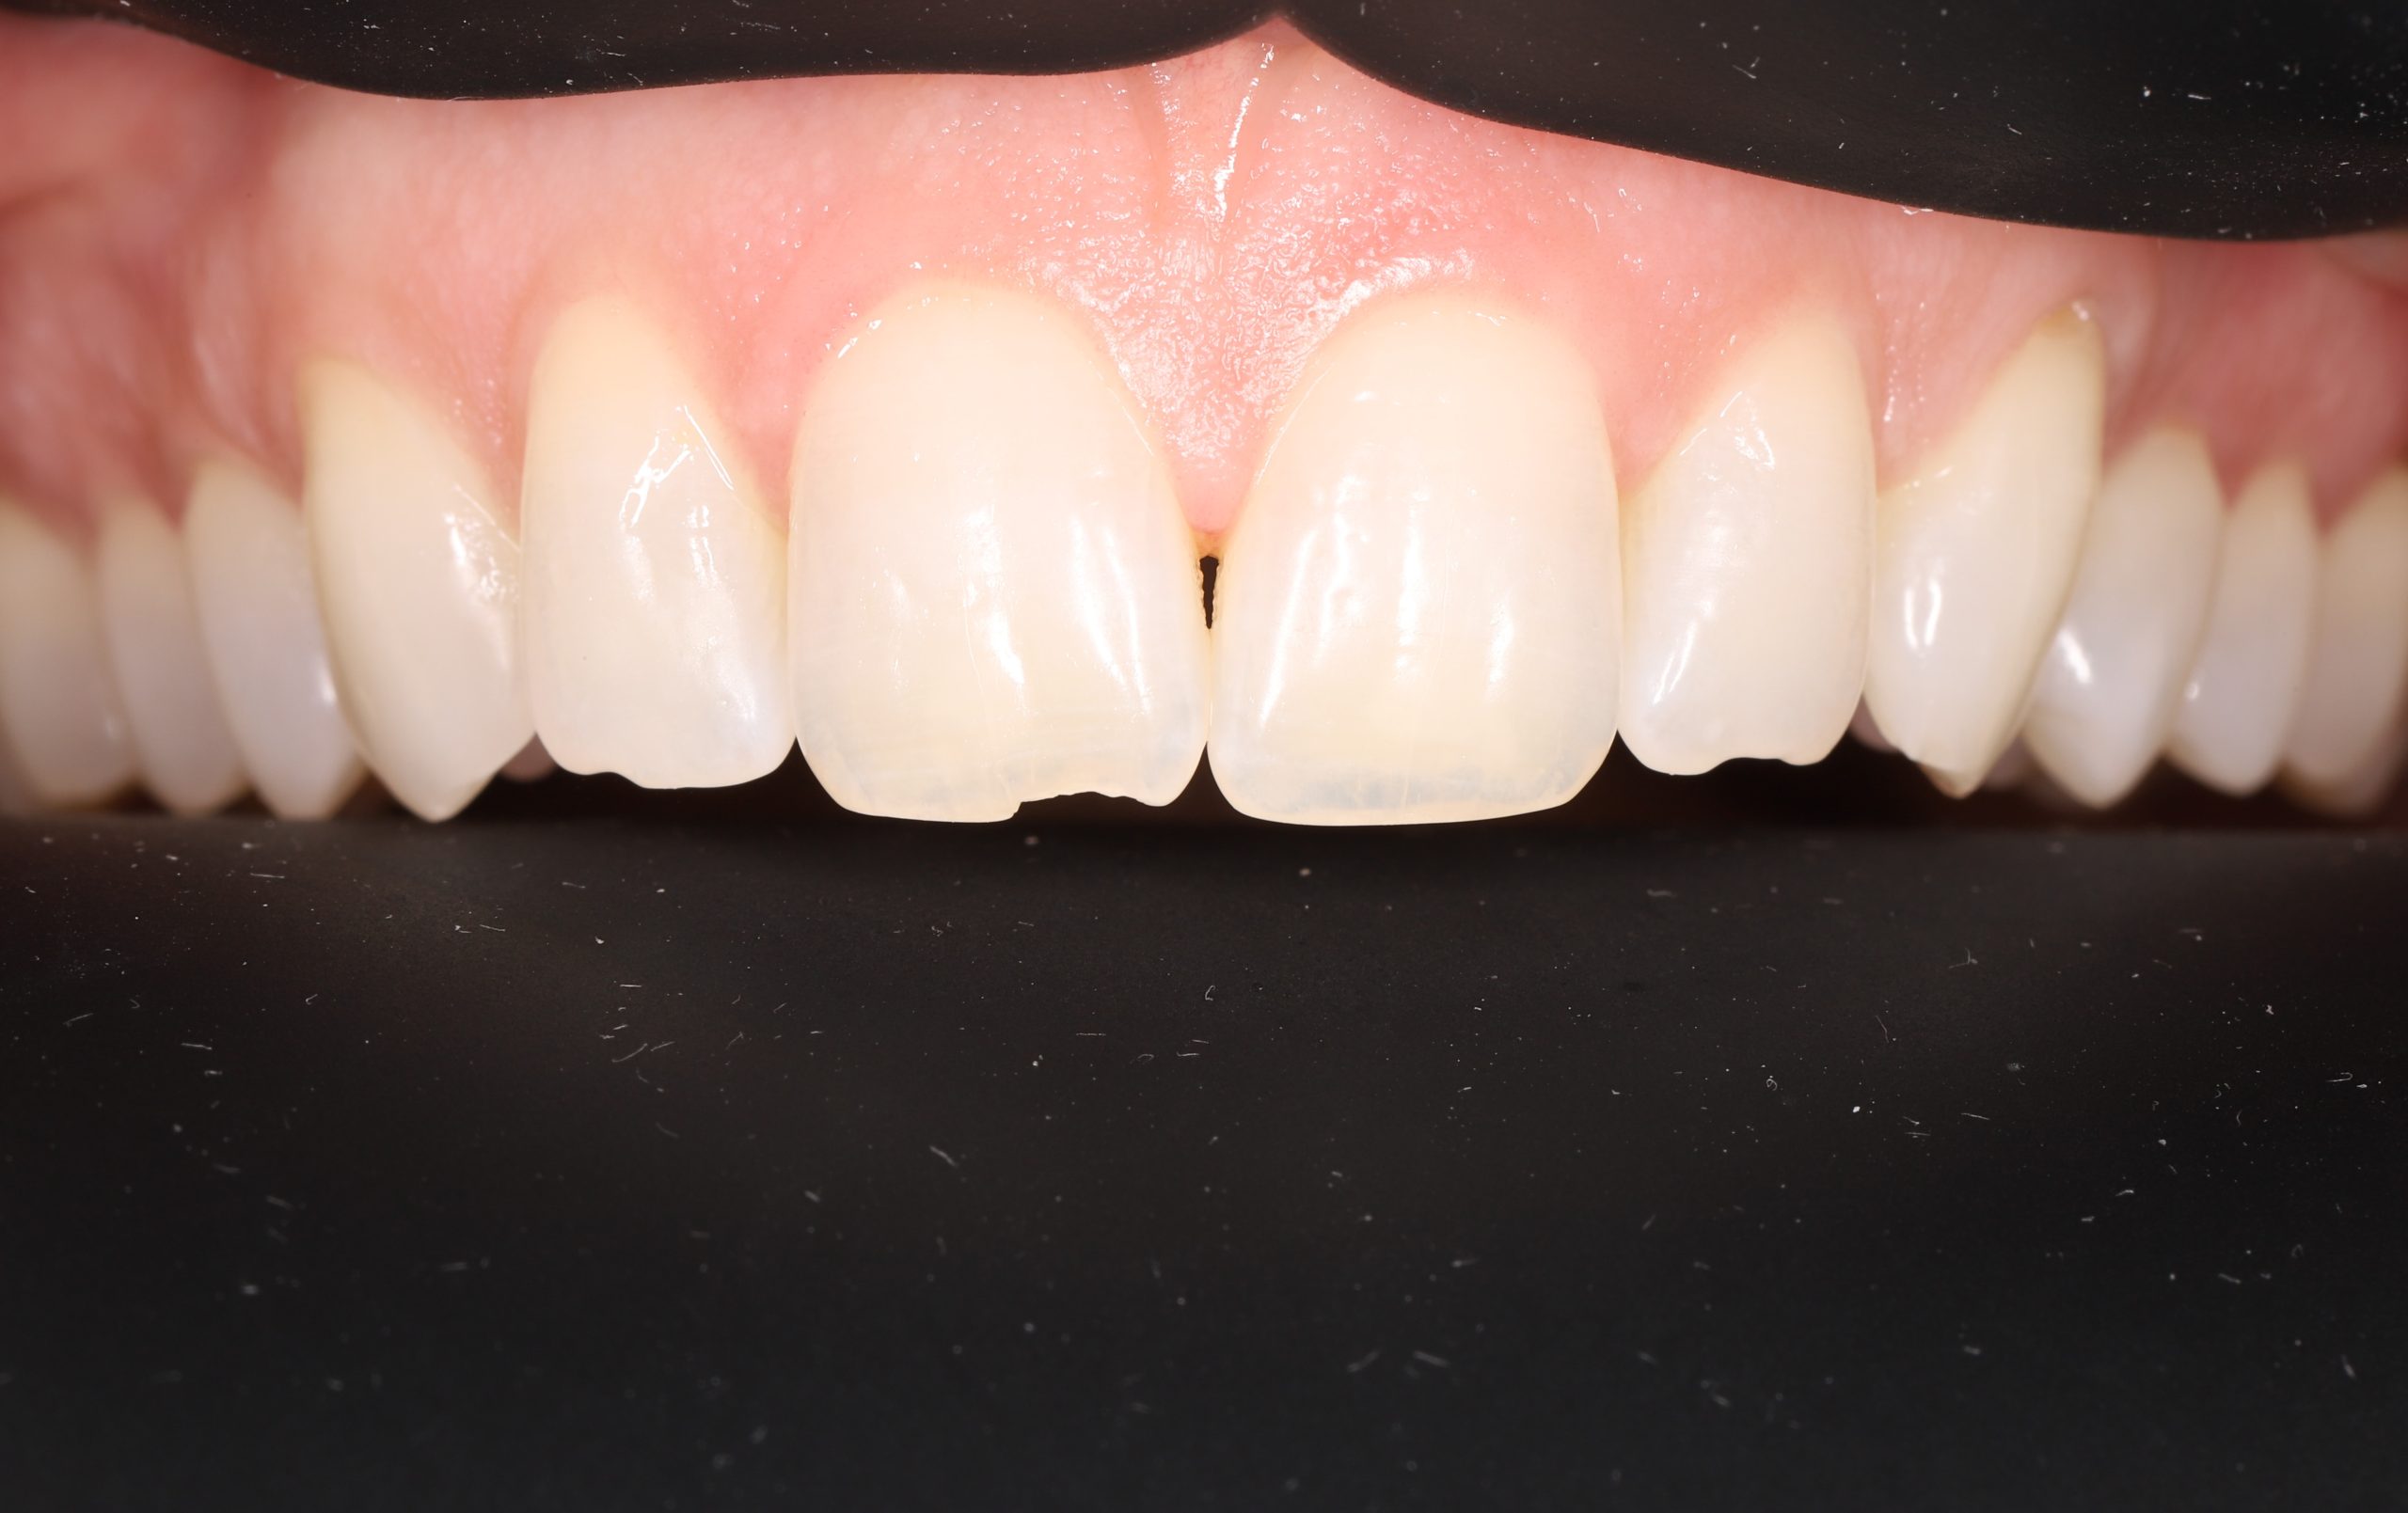

• fixing chipped or worn edges

• closing minor gaps

The tooth-coloured resin is applied in thin layers and shaped carefully to match natural anatomy. For front-tooth work, we may combine several shades for a lifelike result.

The material matches your enamel, blending into the smile with virtually invisible transitions.